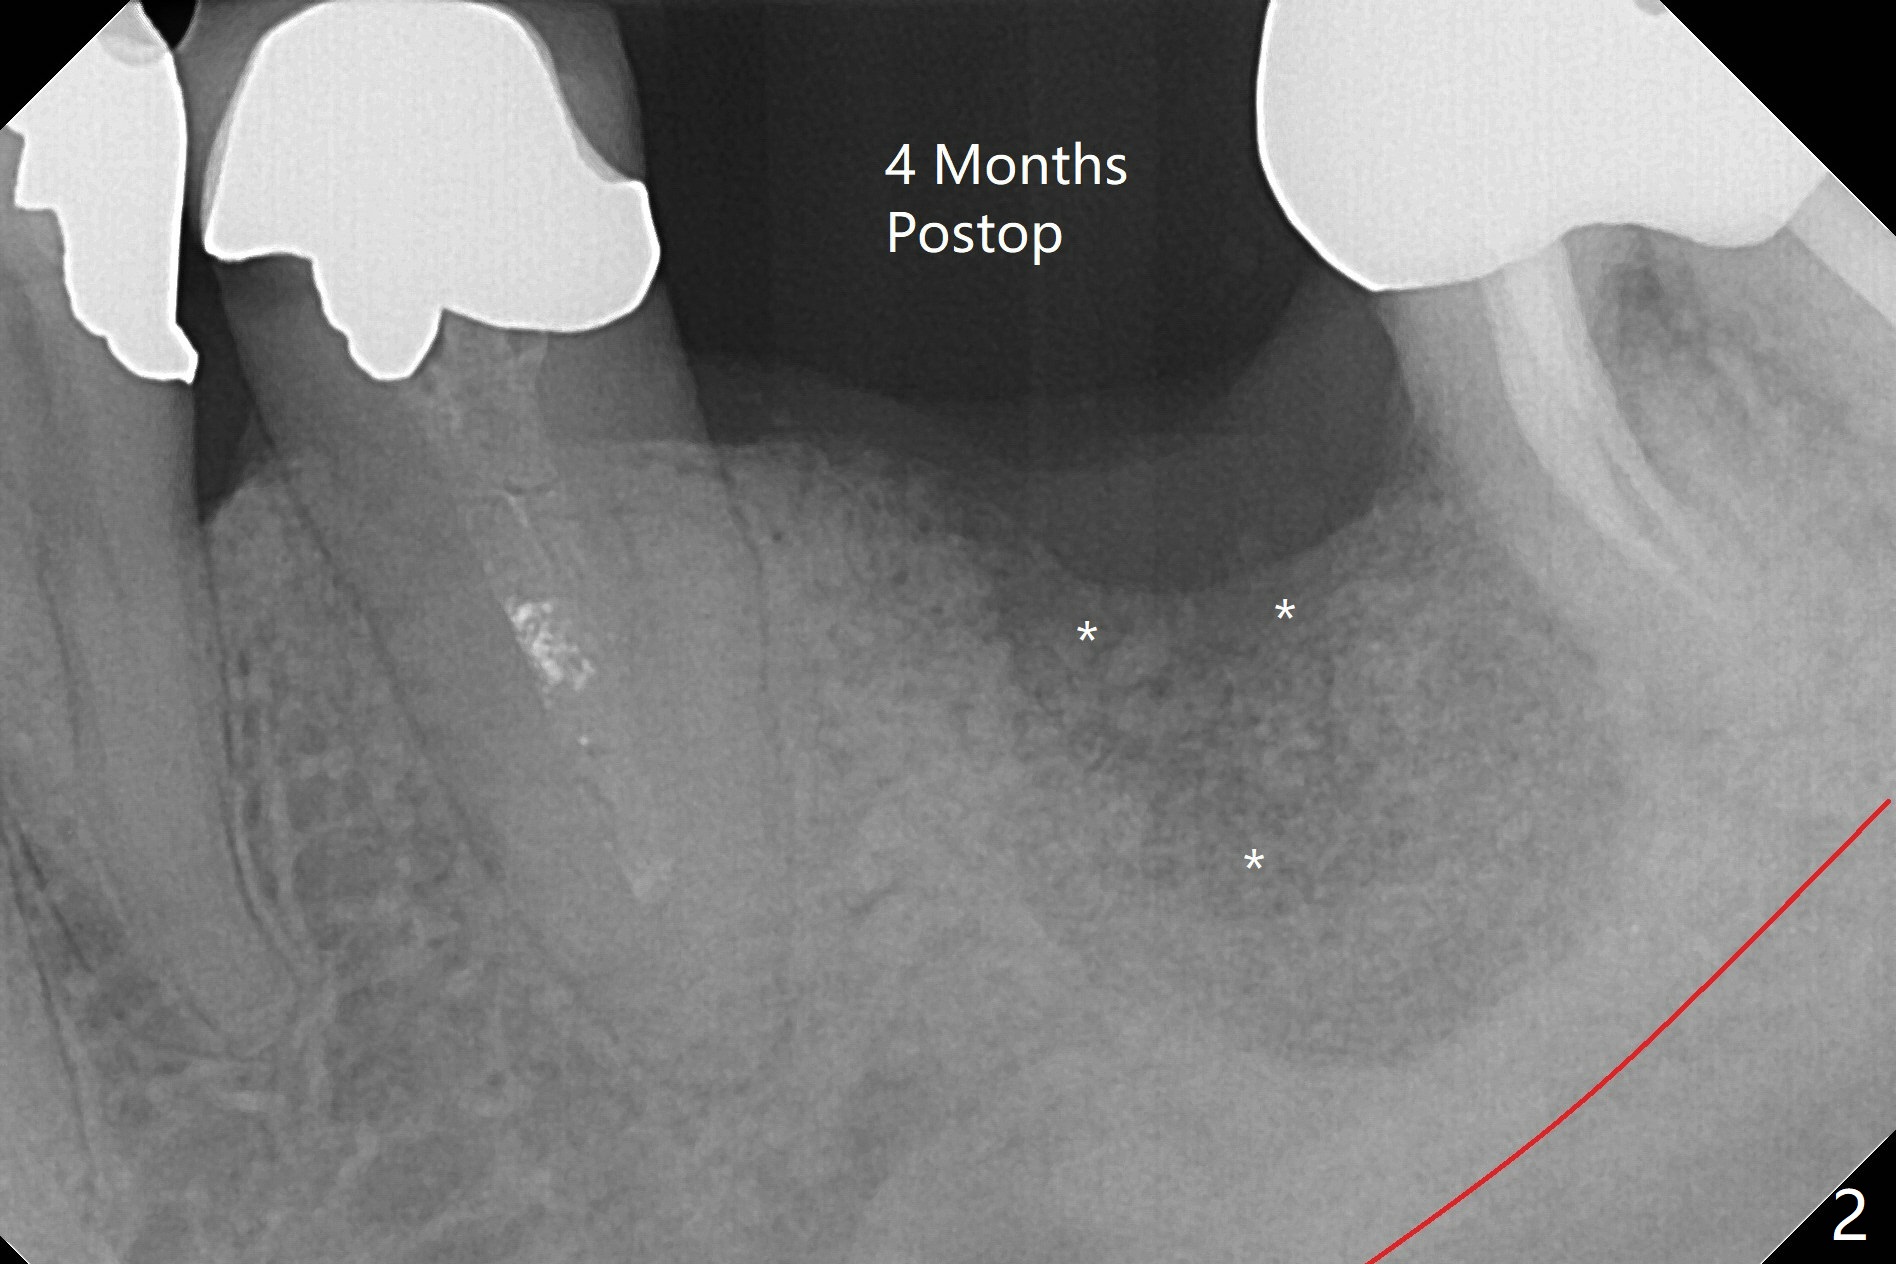

Incompletely Healed Bone Graft

When the patient returns 4 months post implant removal and bone graft, the ridge at #19 is concave with a small hole which communicates with the underlying bone (Fig.1 <). The low density bone in the middle of the socket is ignored (Fig.2 *, 3 S (soft)). With under drilling, primary stability of tissue-level taps is lower. A bone-level dummy implant is placed with low torque (Fig.4). After removal of granulation tissue distal to the osteotomy, a larger implant is inserted with ~15 Ncm; mixture of autogenous bone and allograft is packed (Fig.5 *). The latter is covered by 12x12 mm BioXclude and sutured with 4/0 Chromic Gut tension free. 植牙后6.5月牙槽嵴饱满,角化龈宽(图六(刚开始浸润麻醉))。术后6.5月切开证实植体上面没有骨质覆盖(如图七:*),第一螺纹可能暴露(>)。由于骨质吸收,大号基台置入没阻挡,或者困难(图八),第一螺纹暴露(>)需要再次植骨(图九:*)。放置大号基台(6x6(4)毫米)和植骨使萎缩牙槽嵴部分得到修复(图十,与Uncover前(图六)对比)。Uncover时即刻置入修复性基台好处是利用基台牙龈外部分强化牙周敷料固定,基台中央放置一个棉球后,敷料可以插入基台中央进一步增加固位(图十一(舌侧观):*)。